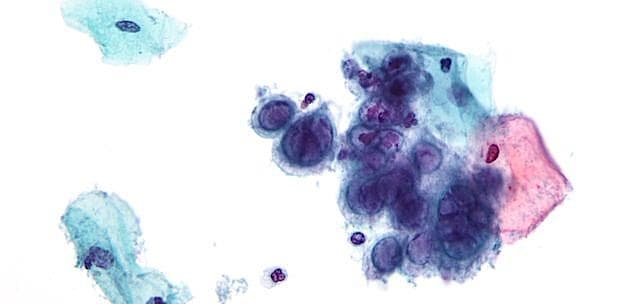

Ved herpes genitalis er risikoen for recidivudbrud 25-50% for herpes simplex-virus type 1 (HSV-1) og 80-90% for HSV-2. Personer med mange og/eller svære recidivudbrud anbefales profylaktisk antiviral behandling, men behandlingseffekt og præparatvalg har givet anledning til tvivl.